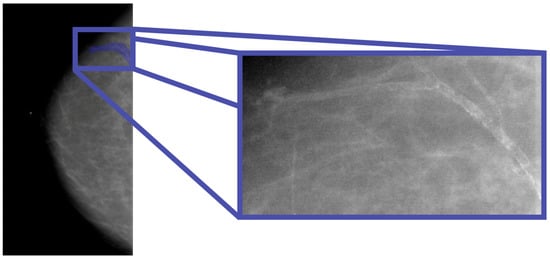

3.2. Preprocessing Results

3.3. Machine Learning-Based Radiomics